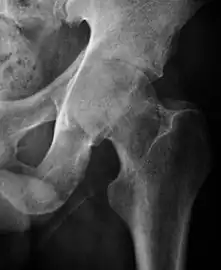

Plain radiography allows us to categorize the hip as normal or dysplastic or with impingement signs (pincer, cam, or a combination of both). Besides these, pathologic processes like osteoarthritis, inflammatory diseases, infection, or tumors can also be identified (Figure 1).[1]

Figure 1.

Radiography in normal hip

X-ray in pincer impingement type of hip dysplasia

X-ray of cam

Hip in osteoarthritis

Septic arthritis